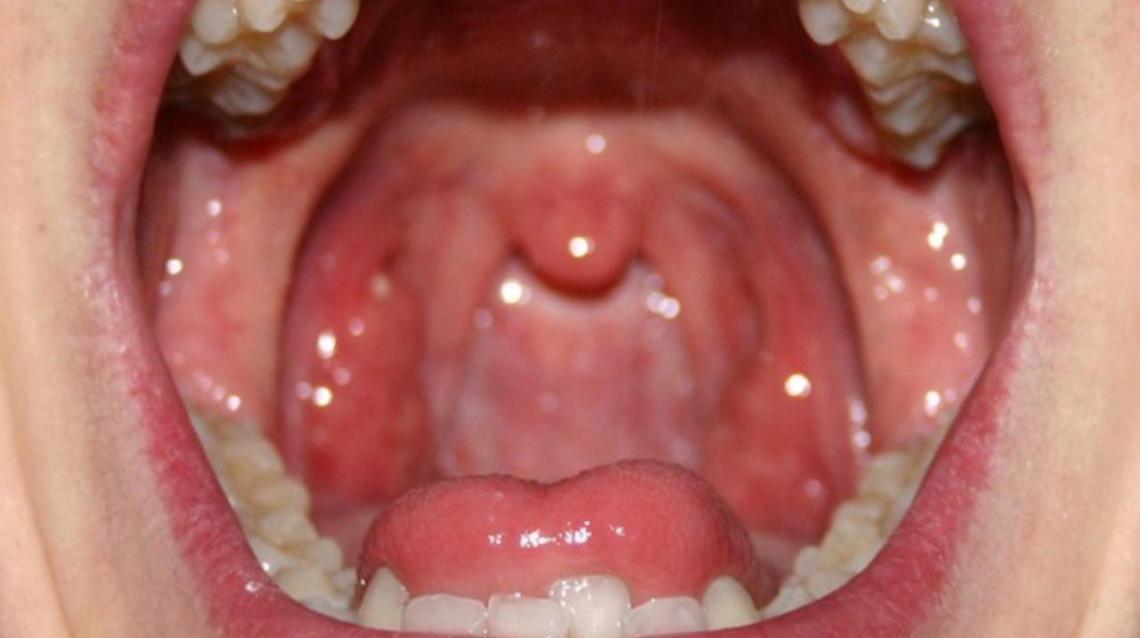

Red Spots On Roof Of Mouth Causes And Other Symptoms

Epstein Pearls In Infants Causes Symptoms Treatment